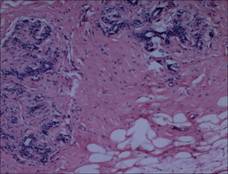

[設(shè)備圖片&實拍顯微圖片]

實拍示范圖片

實拍設(shè)備圖片(MC50+奧林巴斯BX43)